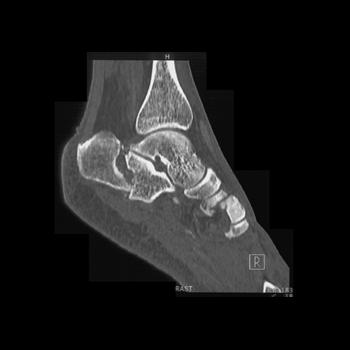

Foot Pathology: Calcaneal fractures

The calcaneus is the most commonly fractured tarsal bone. Calcaneal fractures are classified as intraarticular and extraarticular. The intraarticular fracturesaccount for 70-75% of calcaneal fractures and carry a worse prognosis. The inciting trauma is usually a fall or motor vehicle accident, and these fractures are bilateral in 10% of cases. Concomitant ipsilateral lower extremity fractures are present in 20-46% of cases, and spinal fractures in 10-30%. Extrarticular fractures (Figure: extraarticular fracture of calcaneus) account for 25-30% of calcaneal fractures, and are the sequela of a twisting injury. Anatomic regions affected include the anterior or medial process, the sustentaculum tali, the body or the tuberosity. Severe fractures are readily evident on conventional radiographs; however, CT is essential for elucidating the extent of injury. The intraarticulur fractures are often comminuted and may be displaced. CT is also used for follow up after fracture treatment. CT is very helpful for detecting fracture malunion or nonunion . In addition, the presence and extent of secondary osteoarthritis is readily detected by CT. Several features of intraarticular fractures which can be elucidated on CT have been shown to correlate with the outcome. A central depression fracture has a worse prognosis than a tongue-type fractures, but a better prognosis than a comminuted fracture. An unsatisfactory result is more likely in the setting of subtalar incongruity, decreased fibulocalcaneal space and osteoarthrosis of the talonavicular joint and the ankle.